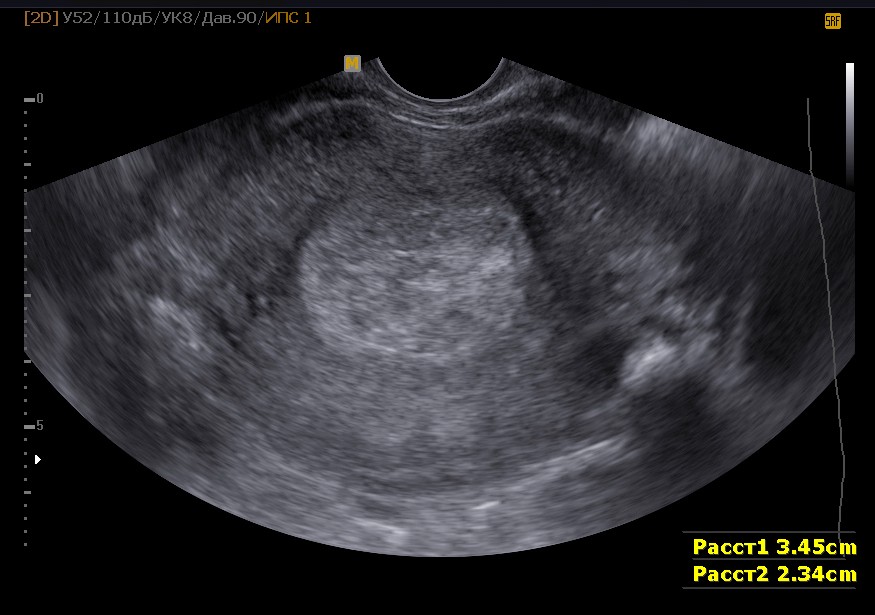

Как же осуществляется данное исследование? В зависимости от того, имеется ли беременность или нет, оно может осуществляться немного по-разному. В частности, речь идет именно о методе исследования. При отсутствии беременности почти всегда используется трансвагинальный метод, так как с его помощью удается достичь максимально близкого расположения датчика к исследуемой области. В результате информативность такого исследования гораздо выше, чем трансабдоминального (в большинстве случаев), при котором картина менее четкая.

Во время исследования пациентка снимает верхнюю одежду и располагается в гинекологическом кресле, на которое заранее укладывается одноразовая простыня, пеленка или полотенце. В влагалище вводится трансвагинальный датчик УЗИ, предварительно помещенный в презерватив и обработанный специальным гелем. Процедура занимает около 10-15 минут, в ходе которой врач визуализирует как шейку матки, так и ее тело. Этот метод позволяет не только оценить биометрические параметры, но и выявить возможные патологии, такие как новообразования или отклонения в состоянии эндометрия и т. д.

Значение такого исследования на разных сроках беременности очень велико. Проводиться оно может трансвагинальным или трансабдоминальным методом. На ранних сроках, обычно, применяется первый способ, как более информативный. На более поздних – второй способ также становится достаточно информативным. Но такое исследование обязательно необходимо выполнять строго на полный мочевой пузырь, так как только таким образом достигается максимальная визуализация исследуемого органа.